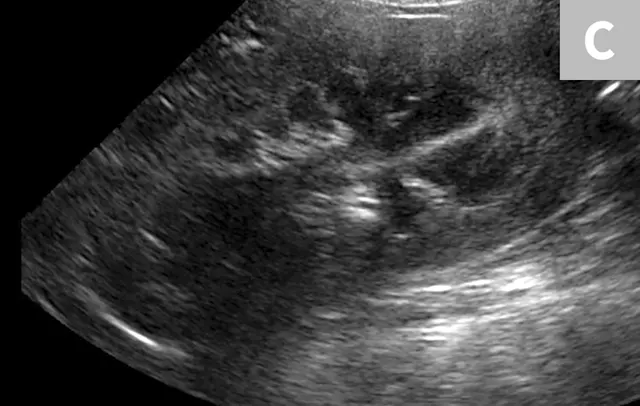

Clinical signs associated with ureteral calculi may range from chronic non-specific signs to acute or chronic renal failure. The presence of hydronephrosis can be highly suggestive of a ureteral obstruction (Figure 6).

FIGURE 6A

Mild to moderate right hydronephrosis and proximal ureteral dilation in a Dalmatian.